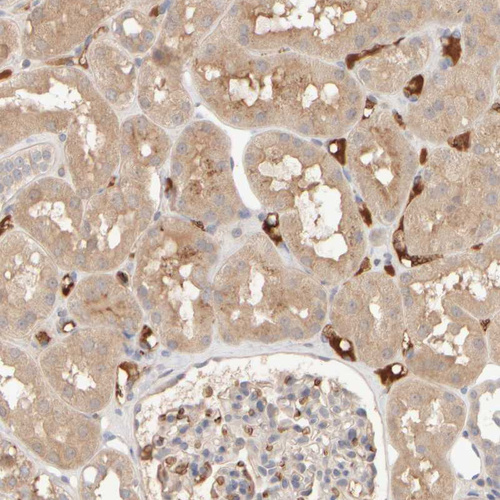

Immunohistochemical staining of human liver shows strong cytoplasmic positivity in hepatocytes.